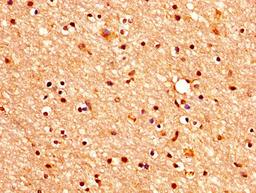

IHC image of CSB-PA005383LA01HU diluted at 1:400 and staining in paraffin-embedded human brain tissue performed on a Leica BondTM system. After dewaxing and hydration, antigen retrieval was mediated by high pressure in a citrate buffer (pH 6.0). Section was blocked with 10% normal goat serum 30min at RT. Then primary antibody (1% BSA) was incubated at 4°C overnight. The primary is detected by a biotinylated secondary antibody and visualized using an HRP conjugated SP system.